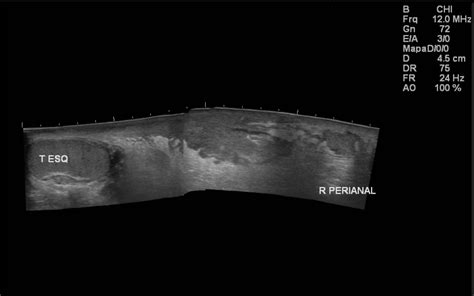

The condition primarily affects the superficial and deep fascia of the perineal, genital, and perianal areas. If not halted immediately, the infection can track along the fascial planes, extending toward the abdominal wall or the thighs, causing systemic toxicity that leads to multi-organ failure.

Diagnosis is primarily clinical, but imaging plays a vital role in confirming the extent of the spread. Computed Tomography (CT) scans are the gold standard for detecting subcutaneous gas and identifying the depth of the fascial involvement, which aids surgeons in planning the scope of the necessary debridement.